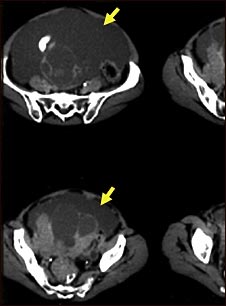

Ascitis con cáncer ovárico; TC

Esta TC del abdomen bajo muestra una cantidad masiva de líquido intraperitoneal (ascitis) en una paciente con cáncer de ovario.